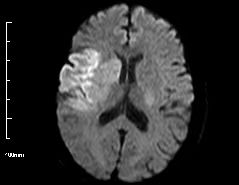

烟雾病主要表现为大脑缺血和出血两个方面。

儿童患者常见症状为缺血症状(约为81%),常因患儿哭闹或剧烈运动(用力或过度换气)时,出现头晕头痛、手脚麻木无力等表现,家长容易忽视。

成年患者中出血更常见,约为60%,多数为平时无高血压病史,突然表现为脑室内出血或蛛网膜下腔出血、脑出血等,往往给患者带来严重的神经功能损害。